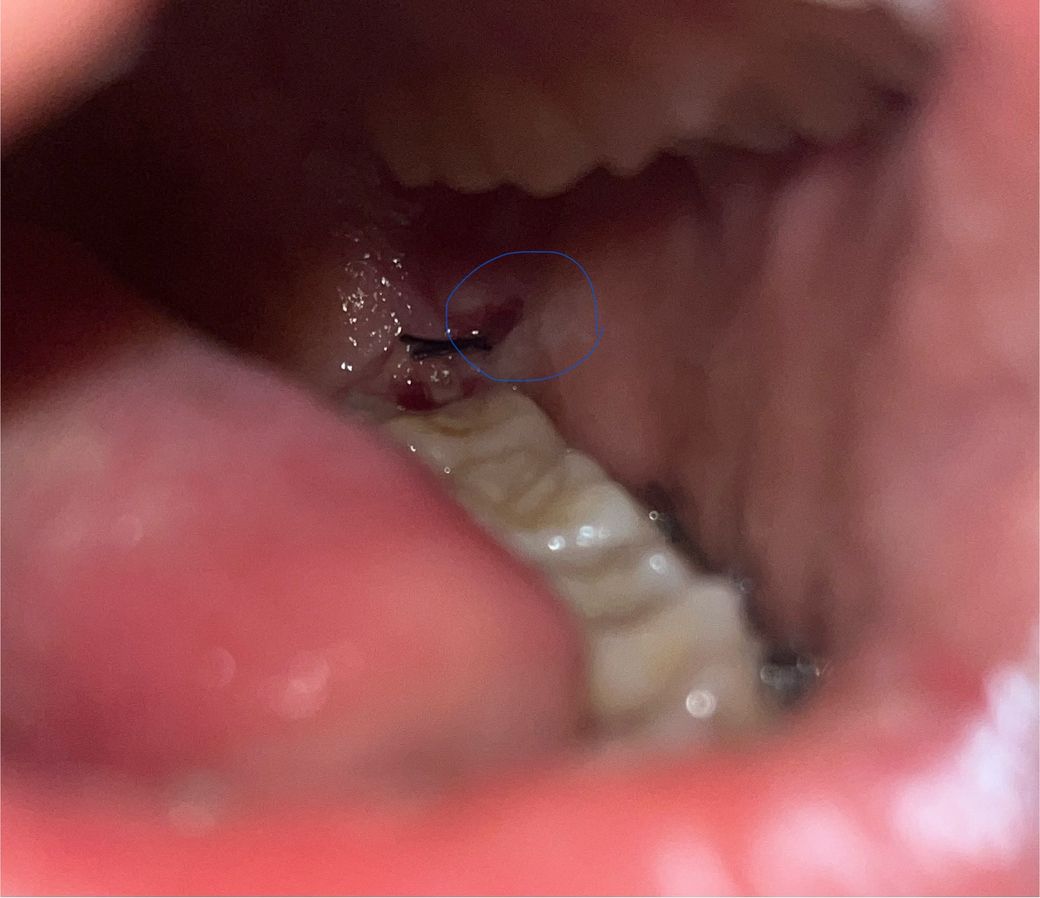

매복사랑니 발치 5일차 잘낫고있나요?

1. 동그라미 친 부분이 찢어졌는데 괜찮을까요?

정상적인건가요?

2. 잘낫고있나요?

5. 사진으로 보기에 염증이 생긴것같나요?

1,찢어진 것이 아니라 아직 상처가 덜 아문 것입니다.

2, 정상적으로 아물고 있습니다.

5,염증 소견 안보입니다.

1. 살짝 잇몸상처가 벌어져 있어도 1~2주 정도면 아물기 시작합니다.

2. 특별히 치유 부전의 양상은 보이지 않습니다.